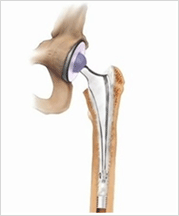

엉덩이 관절을 이루는 골반의 비구나 대퇴골의 머리부분이 닳거나(퇴행성 질환) 특정질병에 의해 괴사되거나, 충격등에 의해 손상된 관절을 모두 인공으로 만든 삽입물로 교체하는 시술을 말한다. 인공 엉덩이관절 치환술의 수술 대상으로는 퇴행성 관절염, 류마티스성 관절염, 대퇴골두 무혈성괴사등으로 인한 고관절(비구,대퇴골의 머리부분)의 손상이 심한 경우 일차적인 수술 대상이 되지만 병이 있다고 해서 모두 수술해야하는 것은 아니다. 어느 정도의 관절에 문제가 있더라도 심한 통증이 없는 경우에는 인공 관절 시술을 받을 필요가 없다. 가만히 있을 때도 아프며 통증으로 인하여 생활이 잘 안되고 잠을 못 자는 경우, 통증이나 관절구축으로 인하여 고관절의 움직이는데 제한이 심한 경우가 그 대상이 된다. 또한 최근 인공 관절 재질의 발달로 시술을 받는 나이 제한이 어느 정도는 둔화 되었지만 그래도 가능한 한 젊은 나이는 피하는 게 좋다.